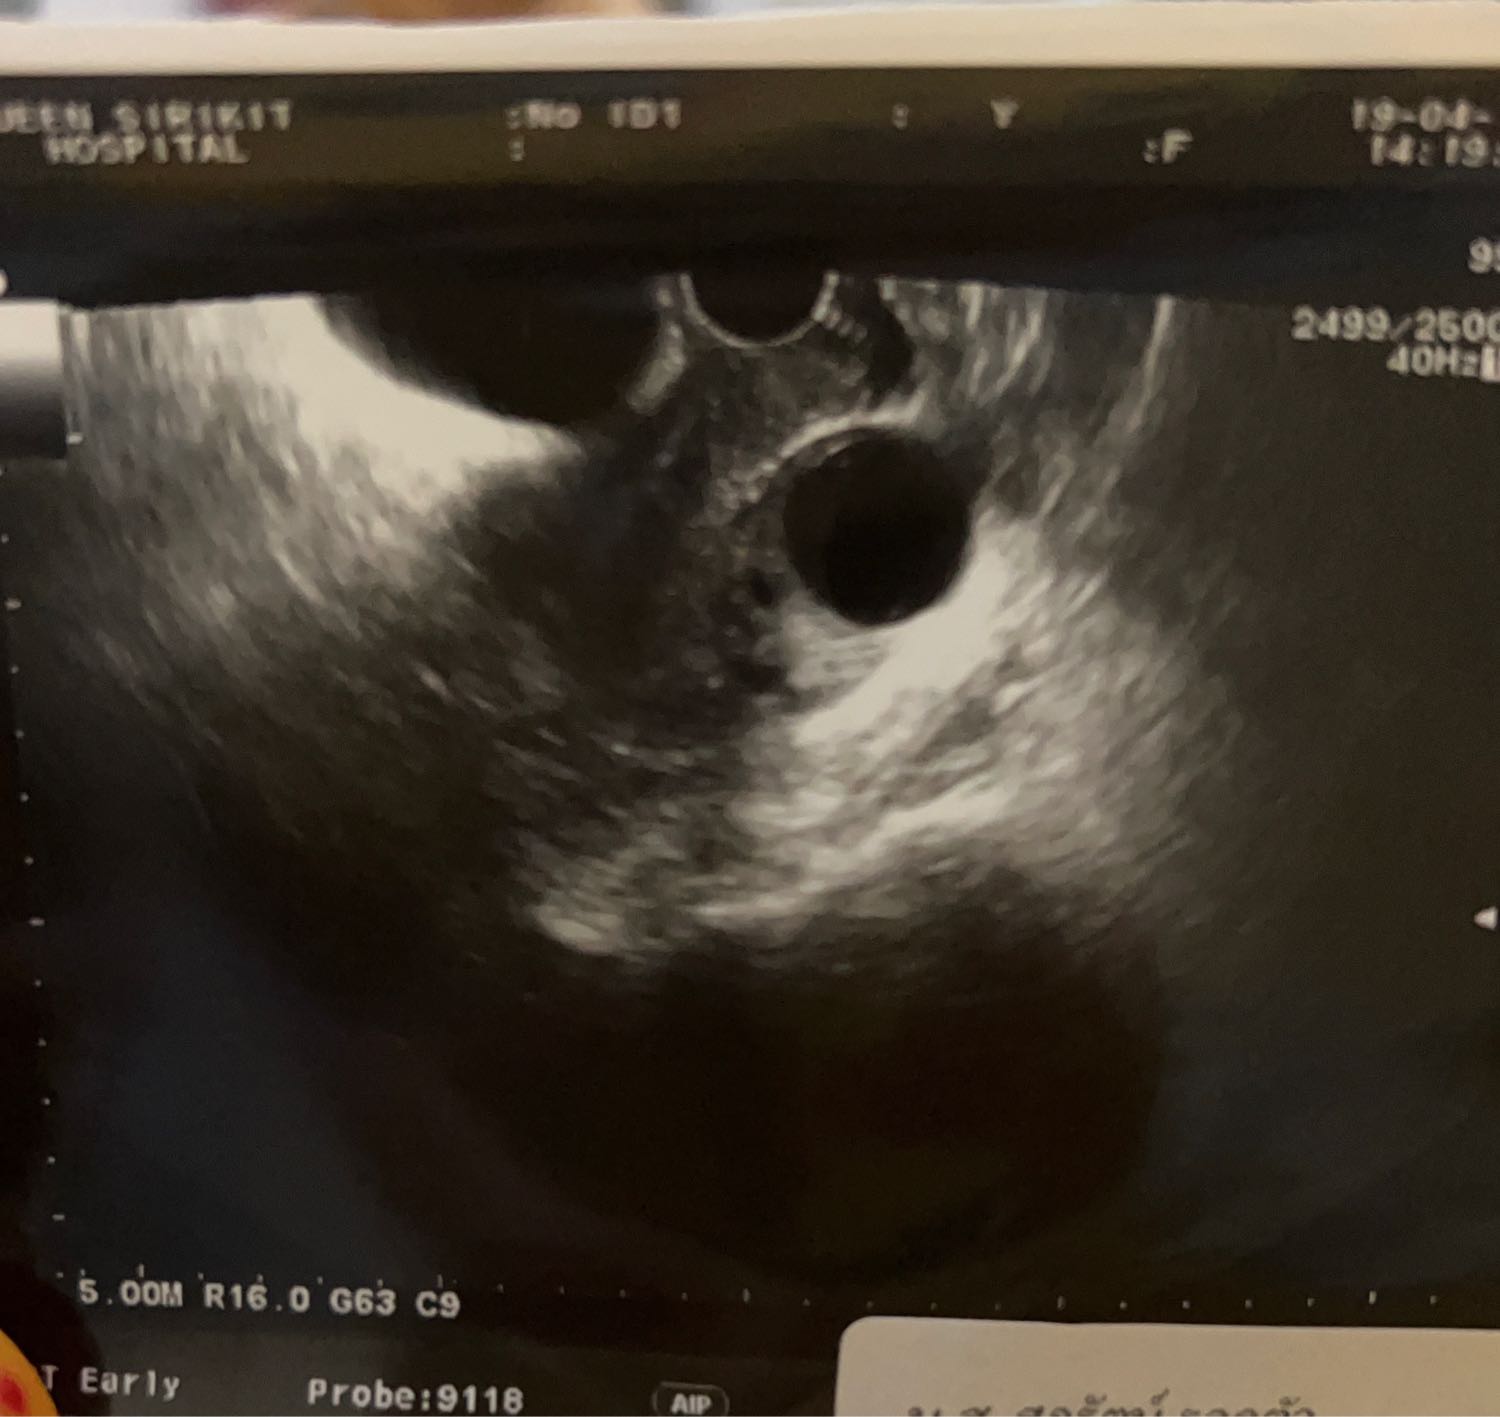

ตรงไหนคือถุงการตั้งครรภ์

พอดีเราสงสัยคะ ว่าตรงไหนคือถุงการตั้งครรภ์ คุณหมอซาวให้ทางช่องคลอดคะ แต่ไม่ได้บอกว่าอันไหนถุง บอกแค่ว่าพบถุงคะ แม่ๆท่านอื่นมีความคิดเห็นยังไงกับภาพซาวของเราบ้างคะ ละตรงไหนคือถุงการตั้งครรภ์คะ